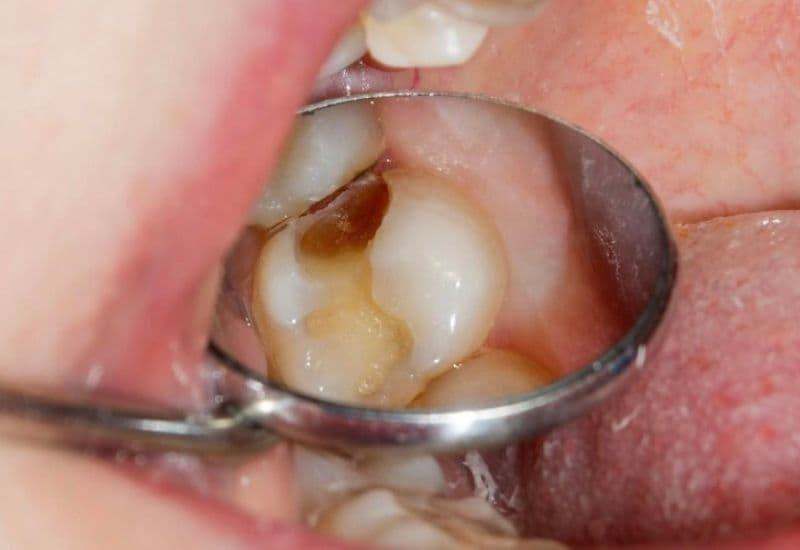

Sâu răng đến tủy là tình trạng vi khuẩn từ lỗ sâu ăn sâu vào lớp ngà và lan tới phần tủy răng – nơi chứa nhiều dây thần kinh và mạch máu. Khi vi khuẩn xâm nhập vào tủy, vùng này sẽ bị viêm nhiễm, gây đau nhức nghiêm trọng và dễ dẫn đến hoại tử nếu không được điều trị đúng cách. Tủy răng bị viêm thường là hậu quả của việc không điều trị sâu răng sớm, để tình trạng kéo dài khiến vi khuẩn phát triển mạnh và lan rộng.

Khi tủy răng bị tổn thương hoặc chết, cấu trúc bên trong răng sẽ thay đổi, dẫn đến hiện tượng đổi màu rõ rệt. Răng sâu đến tủy thường có màu xám, nâu sẫm hoặc đen, khác biệt hẳn so với các răng còn lại. Dù bề mặt răng có thể không xuất hiện lỗ sâu rõ ràng, nhưng sự đổi màu bên trong là dấu hiệu cho thấy tủy đã bị viêm nặng hoặc hoại tử. Đây thường là biểu hiện muộn của sâu răng, đi kèm với các triệu chứng như đau nhức hoặc sưng nướu, cho thấy tình trạng đã trở nên nghiêm trọng và cần điều trị ngay.